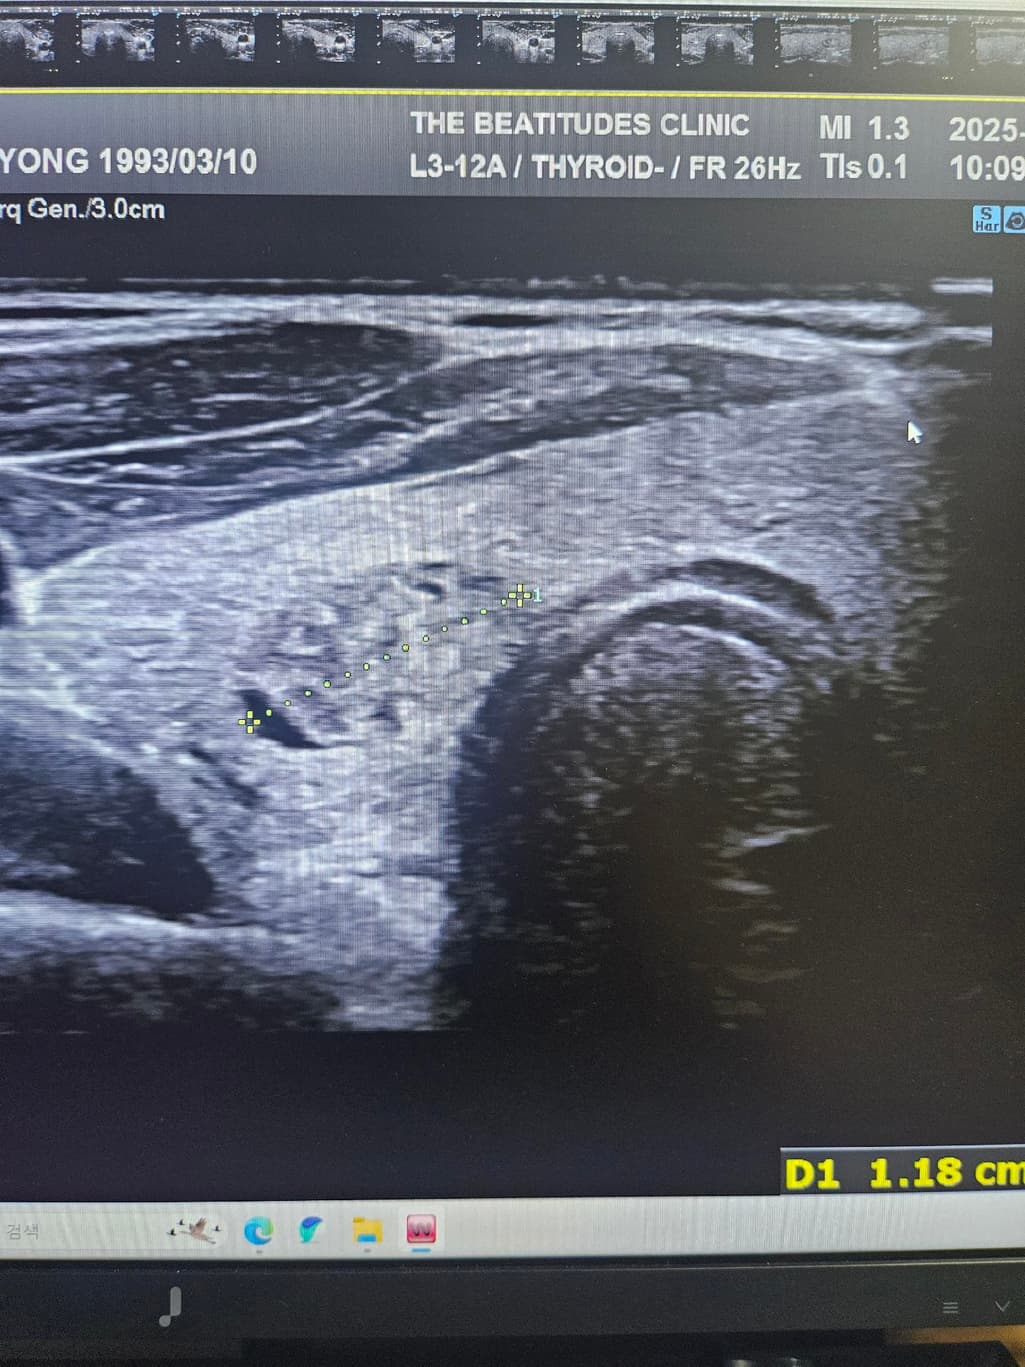

갑상선초음파하고 세침검사 권유받았는데 위의 세개의 사진은 같은 혹이 맞는건가요? 1개 있다고 얘기해줘서 봤는데 사이즈가 이렇게나와서 가로 세로 폭 값인건지 여쭤보고싶습니다

첫번째 사진과 세번째 사진의 경우 같은 결절로 보입니다.

초음파에서 첫번째, 세번째 사진의 급성 연골 오른쪽에 위치한 오른쪽 갑상선에 동그란 혹이 관찰되며 사진으로는 사이즈를 정확하게 구하기 어렵지만 1.5 cm 이상으로 보이며 혹 안에 균질하지 않은 모습으로 악성 혹은 양성이라고 해도 정기적으로 관찰해야 하는 종양으로 보여 조직 검사를 받는 것은 필요한 것으로 보입니다. 갑상선 종양은 다른 종양에 비해 예후가 좋아 적절한 치료를 받으면 대부분 완치가 가능합니다